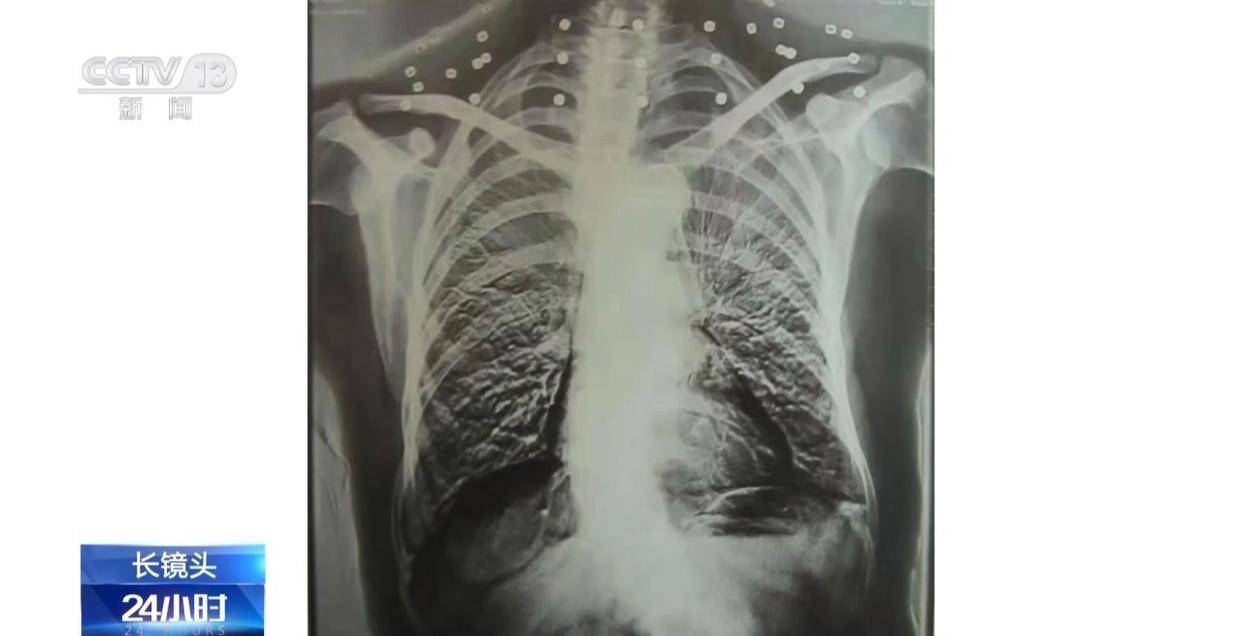

这张CT照片是82岁吴以先老人的CT照,当初拍片时,医生说,“老先生,您要把项链取下来再做CT。”

吴以先老人跟医生说,“可我从来没戴过项链,怎么会有项链呢?你看会不会是弹片?”自此,引出了一段老人不平凡的往事。

二十年前,吴以先老人做CT检查时发现,他的颈部有许多弹片,医生当时把弹片误认为是老人戴的项链,于是提醒他要把项链取下来再做检查。

这是吴以先老人体内的33颗弹片,也是老人摘不下来的“项链”。